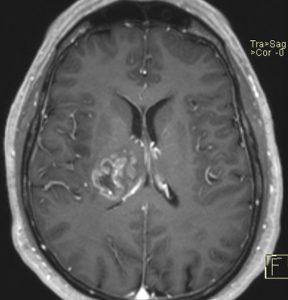

Αριστερά: Μαγνητική τομογραφία εγκεφάλου στην οποία φαίνεται πιθανός κακοήθης όγκος στην περιοχή του δεξιού θαλάμου. Δεξιά: Αξονική τομογραφία αμέσως μετά το τέλος της στερεοτακτικής βιοψίας, στην οποία επιβεβαιώνεται η λήψη ιστού από τη σωστή περιοχή – στόχο (προσωπικό αρχείο νευροχειρουργού Π. Σταυρινού)